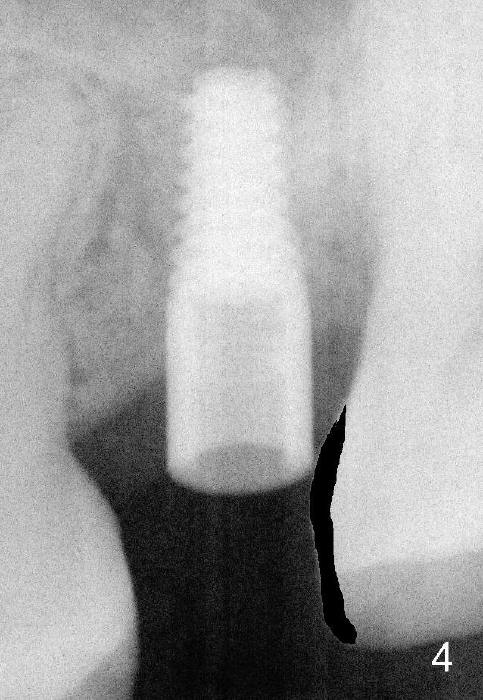

Exam immediately prior to surgery shows that the edentulous ridge is wide buccolingually. The mesiodistal space is less than 6 mm. It appears that a 4 mm implant is appropriate. Two piece implant is chosen over a one-piece one, because of large surface area of the former. After local anesthesia, a 3.5 mm tissue punch is used for access to the bone. A 1.5 mm pilot drill initiates osteotomy 8 mm in length (Fig.1 D). The drill is more or less in the middle of the edentulous space and 1 mm coronal to the sinus floor (^). Then a 2 mm pilot drill, 2.5 mm and 3 mm reamers are used to enlarge osteotomy (8 mm deep). Mixture of autogenous bone and Osteogen and 2.5 mm Bicon osteotome are used for sinus lift. The osteotome does not reach the intended depth of 10 mm. The osteotomy is extended with the 2 mm drill and 2.5 mm reamer (Fig.2 R) to barely perforate the sinus floor. When a 4x11 mm implant is being placed, it tends to deviate distally. The implant is backed up twice: initially it appears to lean mesially, but as it is seated deeper, it is deviated distally again (Fig.3). An immediate provisional has to be fabricated to prevent the space from further narrowing. A 3.5x3 mm abutment is placed. The mesial surface of the tooth #14 (Fig.4 black area) is trimmed for restoration. Why is the implant deviated? How to fix it?